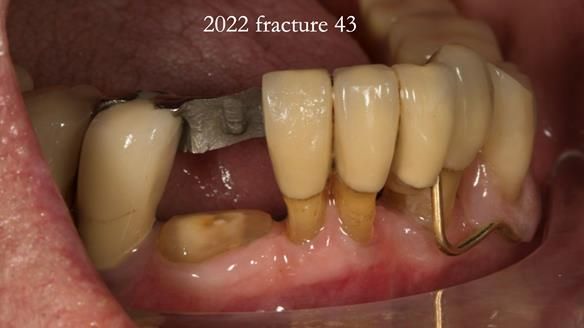

In 2022, tooth 43 fractured.

An artificial tooth was added to the RPD

by welding a cobalt–chrome tag to the bar

and adding the tooth.

The denture continued to function extremely well.